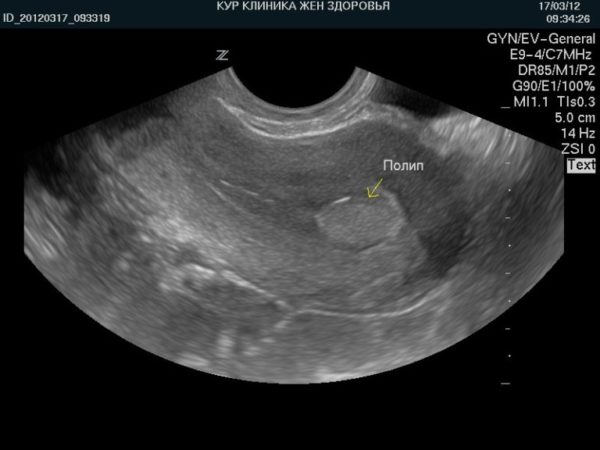

Диагностика заболевания проводится различными способами – цервикальные полипы (образования, находящиеся в шейке матки) можно увидеть на стандартном гинекологическом обследовании в кресле, а наросты, локализованные в полости матки (полипы эндометрия) можно диагностировать при помощи УЗИ, гистероскопии и кольпоскопии.

Что касается локализации полипов, она следующая (указана на фото):

- в шейке матки – цервикальный полип;

- в полости матки – полип эндометрия, в этом случае образование может располагаться на стенках детородного органа или на дне.